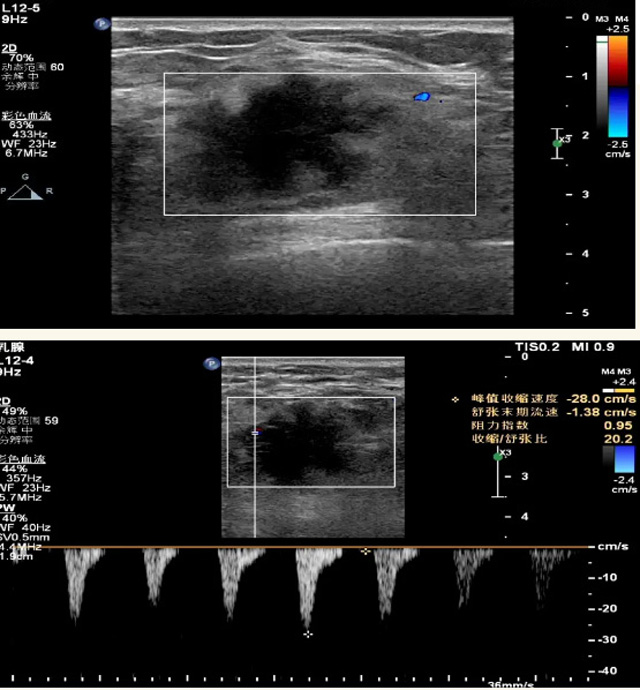

乳腺B超检查无辐射,对囊性病变敏感,可以实时观察病灶。超声引导活检跟手术前的定位。就是它对于微小的钙化查出率比钼靶稍微差点。磁共振MRI检查也是是没有辐射的,对备孕跟已经怀孕的人士比较友好。不用担心这个辐射影响胎儿问题。对乳腺病灶敏感性较高,致密乳腺病灶、乳腺癌的复发,准确鉴别囊性及实性病变。可以帮助临床医生判断恶性、良性病变。但是MRI磁共振对微小钙化不明显,微钙化还是钼靶靠谱点。检查时间比较长,有伪影的影响。费用相对B超,钼靶高很多。

乳腺检查需要避开经期,经期后一周比较合适。设备检查时候压10秒钟左右,不会有很大的疼痛,稍微有点不适应。钼靶辐射剂量小,腺体越厚,所受剂量也会有所增高。次诊断性的X线检查剂量,也达不到能造成胎儿或者胚胎损伤的剂量。乳腺B超跟磁共振MRI就没有辐射。胸小或者假体植入也可以做检查,乳腺组织曝光野内,图像受干扰的情况降到最低,从而保证结果的准确性。